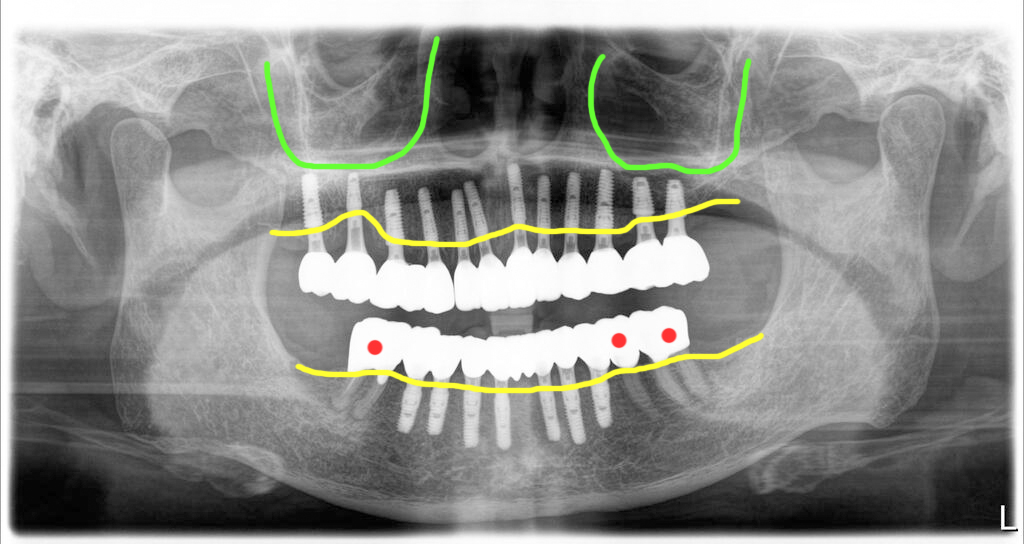

상악은 모두 발치 후 임플란트를 12개 심었고, 좌측 상악동은 측방접근 뼈이식을 하면서 식립을 했습니다. 상악동거상술과 함께 식립된 임플란트는 고정이 부족해서 힐링을 끼워두고 임시치아에 적용하지 않았어요.

아래쪽에 빨강색으로 표시된 부분은 자신의 치아를 살려서 다시 크라운으로 치료한 모습입니다. 그리고 마모로 인해 소실된 고경(위턱과 아래턱과의 높이)도 함께 회복했습니다. 전체 맞춤지대주에 지르코니아로 마무리된 파노라마 엑스레이 사진입니다.